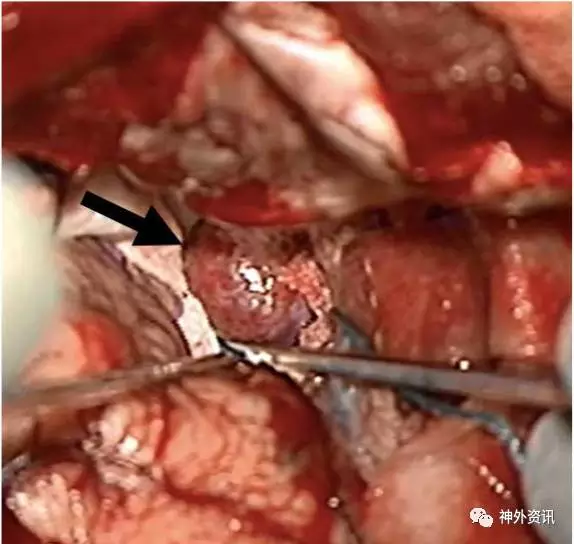

图3. 术中照片可见前床突占位病变,像脑膜瘤;术中分离和切除肿瘤较一般的床突旁脑膜瘤容易。

36岁男性患者。因外伤后行影像学检查,意外发现右侧中颅窝占位病变,无临床症状。术前MRI检查显示,右侧前床突一起源于硬脑膜的肿物,T1加权呈低信号,T2加权呈等信号,增强扫描均匀强化,考虑为脑膜瘤。经右侧翼点入路全切除病灶,无术后并发症。术后病理学检查,见病变为扩张、硬化的血管团,间质无神经组织,血管内有血栓形成,符合海绵状血管瘤。